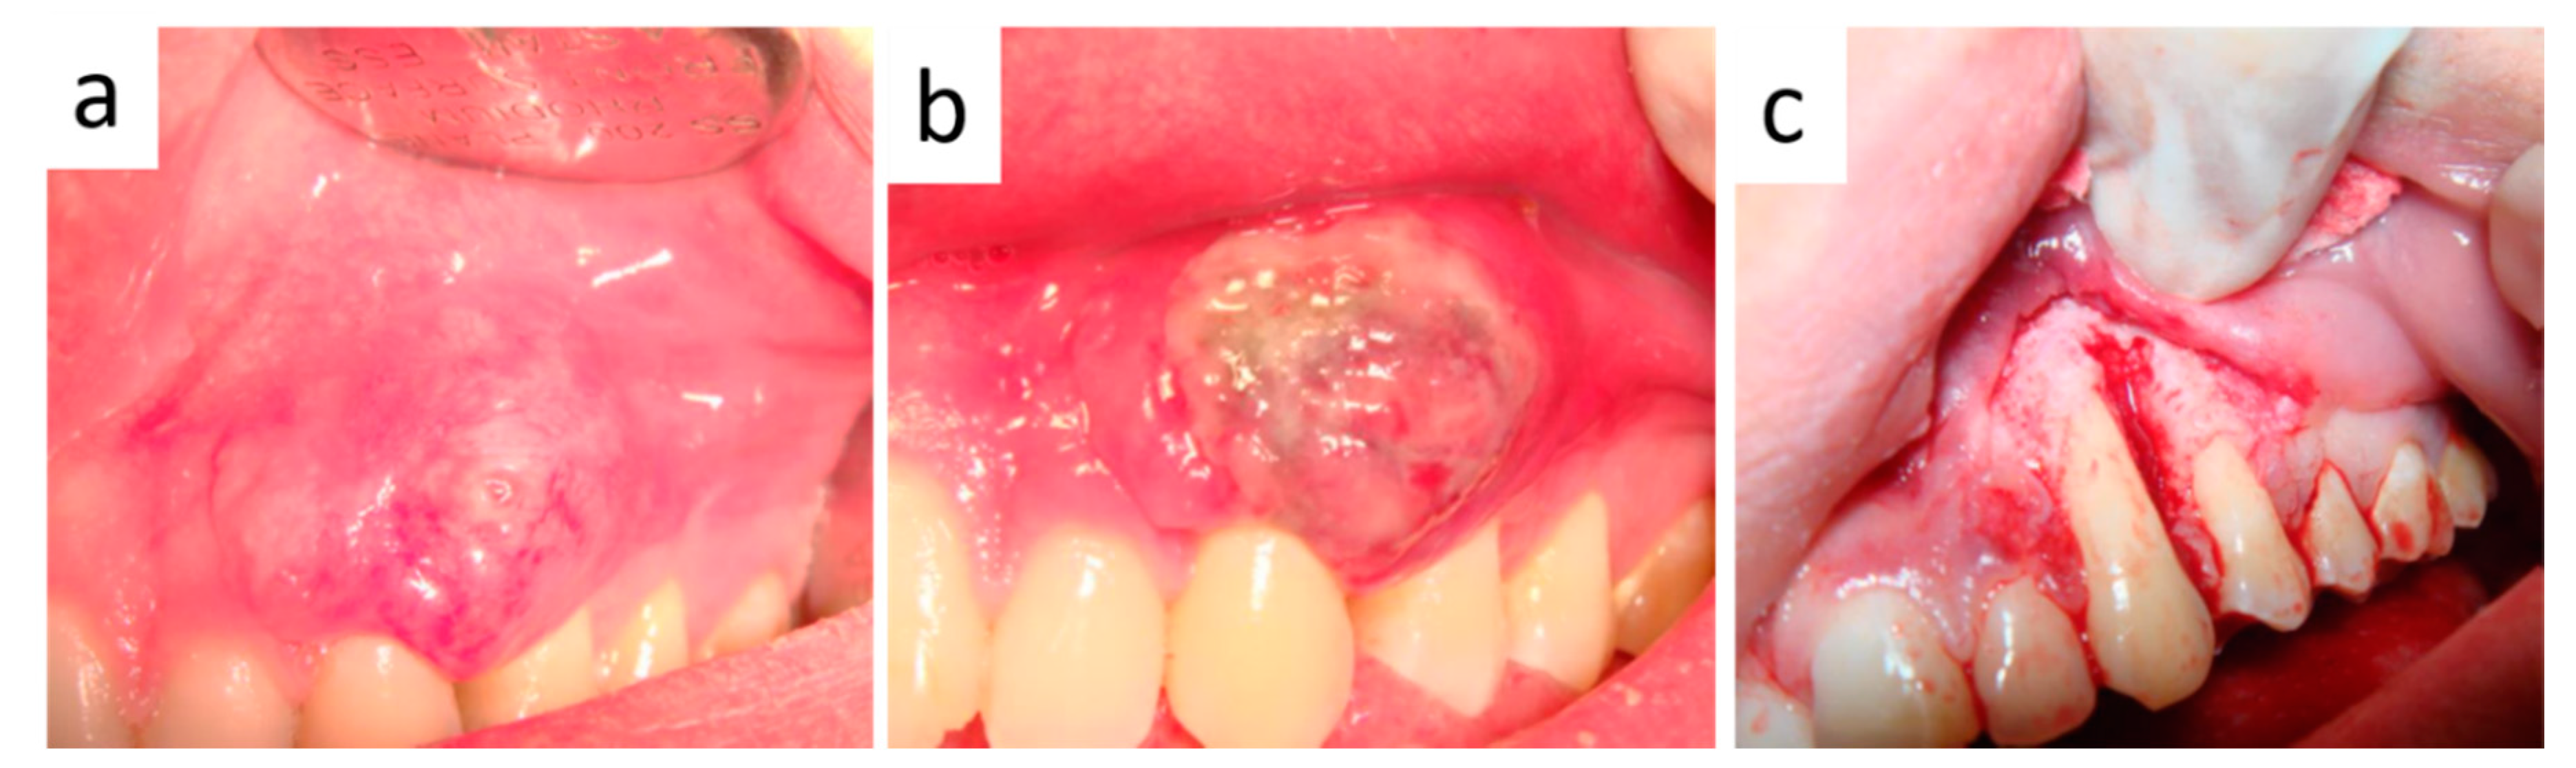

2. Case Presentation